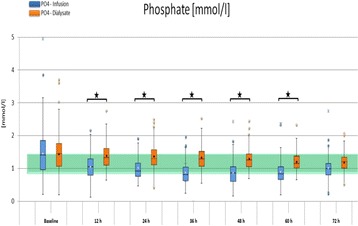

P187 - Severe hypophosphatemia during citrate-anticoagulated CRRT

A. Steuber, C. Pelletier, S. Schroeder, E. Michael, T. Slowinski, D. Kindgen-Milles